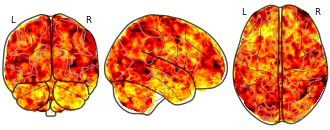

Individual Brain Charting dataset extension, second release of...

- neurovault.org

niftiUpdated Feb 15, 2020+ more versions Share

EmailClick to copy linkLink copied Cite(2020). Individual Brain Charting dataset extension, second release of high-resolution fMRI data for cognitive mapping: sub-06_ses-02_task-hcp_wm_ffx_2back_face [Dataset]. http://identifiers.org/neurovault.image:368774niftiAvailable download formatsUnique identifierhttps://identifiers.org/neurovault.image:368774Dataset updatedFeb 15, 2020License

Cite(2020). Individual Brain Charting dataset extension, second release of high-resolution fMRI data for cognitive mapping: sub-06_ses-02_task-hcp_wm_ffx_2back_face [Dataset]. http://identifiers.org/neurovault.image:368774niftiAvailable download formatsUnique identifierhttps://identifiers.org/neurovault.image:368774Dataset updatedFeb 15, 2020LicenseCC0 1.0 Universal Public Domain Dedicationhttps://creativecommons.org/publicdomain/zero/1.0/

License information was derived automaticallyDescriptionCollection description

The individual Brain Charting (IBC) Project is using high resolution fMRI to map 13 subjects that undergo a large number of tasks: the HCP tasks, the so-called ARCHI tasks, a specific language task, video watching, low-level visual stimulation etc. The native resolution of the data is 1.5mm isotropic. Their main value lies in the large number of contrasts probed, the level of detail and the high SNR per subject. This dataset is meant to provide the basis of a functional brain atlas. We upload here smoothed individual SPMs. The uploaded maps comprise session-specific and fixed effects across maps acquired with AP and PA phase encoding directions.

Note that Neurovault collection #4438 is a subset of that one. In the present collections, some details have been fixed, including mroe accurate and unique file naming.

Subject species

homo sapiens

Modality

fMRI-BOLD

Analysis level

single-subject

Cognitive paradigm (task)

working memory fMRI task paradigm

Map type

Z

- N